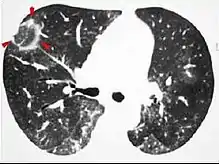

High-resolution CT image showing ground-glass opacities in the periphery of both lungs in a patient with COVID-19 (red arrows). The adjacent normal lung tissue with lower attenuation appears as darker areas.

CT image in patient with COVID-19 showing bilateral ground-glass opacities at the periphery of both lungs.

Ground-glass opacity is among the most common imaging findings in patients with confirmed COVID-19.[16][17] One systematic review found that among patients with COVID-19 and abnormal lung findings on CT, greater than 80% had GGOs, with greater than 50% having mixed GGOs and consolidation.[16] GGOs with mixed consolidation has most often been found in elderly populations.[18] Several studies have described a pattern among initial, intermediate, and hospital discharge imaging findings in the disease course of COVID-19. Most commonly, initial CT imaging reveals bilateral GGOs at the periphery of the lungs. During initial stages, this is most often found in the lower lobes, although involvement of the upper lobes and right middle lobe has also been reported early in the disease course.[16][18] This is in contrast to the two similar coronaviruses, SARS and MERS, which more commonly involve only one lung on initial imaging.[19][20] As the COVID-19 infection progresses, GGOs typically become more diffuse and often progress to consolidation.[11][18] This is sometimes accompanied by the development of a crazy paving pattern and interlobular septal thickening.[18] In many cases the most severe pulmonary CT abnormalities occurred within 2 weeks after symptoms began.[17] At this point, many individuals begin showing resolution of consolidation and GGOs as symptoms improve. However, some patients have worsening symptoms and imaging findings, with further increase in septal thickening, GGOs, and consolidation. These patients may develop lung "white-out" with progression to acute respiratory distress syndrome (ARDS) requiring treatment escalation.[17][21]

Preliminary reports have shown many patients have residual GGOs at time of discharge from the hospital. Due to the novelty of COVID-19, large studies investigating the long-term pulmonary CT changes have yet to be completed. However, long-term pulmonary changes have been seen in patients after recovery from SARS and MERS, suggesting the possibility of similar long-term complications in patients who have recovered from acute COVID-19 infection.[22]